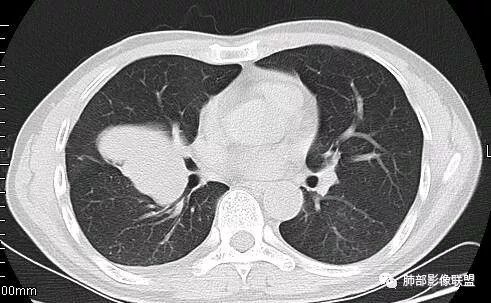

崇军:右侧中叶支气管与下叶支气管夹角处的肿块,支气管没有堵塞仅仅推移,不是支气管来源,纵隔来源也可以排除;跨叶,边界清,平扫无明显坏死,来源只剩下淋巴,血管与胸膜,如果是淋巴,纵隔未见其他淋巴结,淋巴瘤排除,巨淋巴增生症可能,血管来源,PSP可能,胸膜来源,SFT可能,这三者没有增强难鉴别。张帅:病灶边缘光滑,气管挤压呈贴边征,赞同王崇军老师观点:增大淋巴结,但同时需鉴别PSP及类癌。

南边:这类片其实很艰难Shelia:应该有个增强崇军:是的,如果没有老师您以前的讲述,一个肺门占位就发出去了风儿:肿块跨叶生长,边缘光滑,有膨隆有平直,支气管血管受压,病灶后方支气管似乎进入病灶后堵塞,与纵隔胸膜呈锐角,来源肺内-神经内分泌肿瘤?胸膜-SFT?血管-PSP?临近心包少量积液右侧胸腔少量积液是否与肿块有关

南边:病灶边界清,提示侵袭性弱,膨胀生长为主;这时候我们提示病灶不应该是支气管关系密切,提示间叶来源或胸膜来源

3.肿块常常较大,甚至巨大,病灶边界一般清楚,影像上常有假包膜样结构、有膨胀性生长的特点,影像科医师有时甚至会纠结其来源于肺部或是胸壁纵隔。常见的肺癌肿块,很少有机会能长成这样的规模。

4.边缘可以有浅切迹,部分病灶会有铸型样外观,但大体十分圆钝,不会出现典型的分叶和毛刺,也很少会出现胸膜牵拉。支气管常推移,有明显的支气管阻塞时也较少观察到相关的阻塞性炎症。

3.PPS在肺实质内成膨胀性生长,很少侵犯或突破支气管黏膜,影像学表现密度均匀、边缘光整的肿块,少有空洞、分叶、毛刺、钙化,一般为单发,体积较大,直径多在4cm以上,增强后呈不均匀强化。